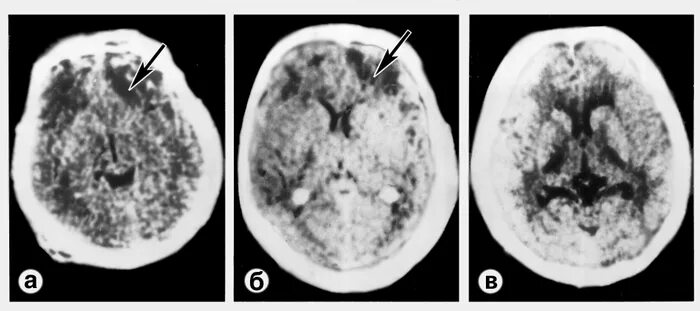

Диффузное поражение головного мозга